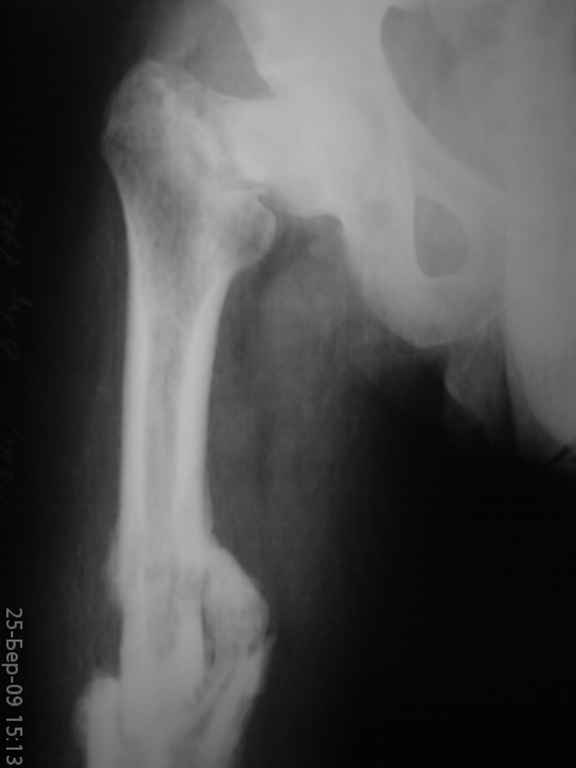

К нам поступил больной,26 лет,травма 6 месяцев назад(падение с

высоты). Лечился консервативно (вытяжение,гипс) по поводу перелома

бедра, перелом шейки был пропущен.

Объективно:ходит с помощью костылей, нога не опорная.Укорочение

приблизительно 6 см, жалуется на умеренные боли при нагрузке в паху и

с/3 бедра.

Ренгенснимки прилагаются(за качество не обессудьте); на КТ с/3 бедра

- формирующийся тугой ложный сустав (извините,не смог представить),

КТ шейки не делали.

Вложение не в текстовом формате было извлечено…

Имя     : DSC00452.JPG

Тип     : image/jpeg

Размер  : 10953 байтов

Описание: отсутствует

Url     : http://weborto.net:8080/pipermail/ortho/attachments/20090329/dbbd3c7a/attachment-0008.jpeg